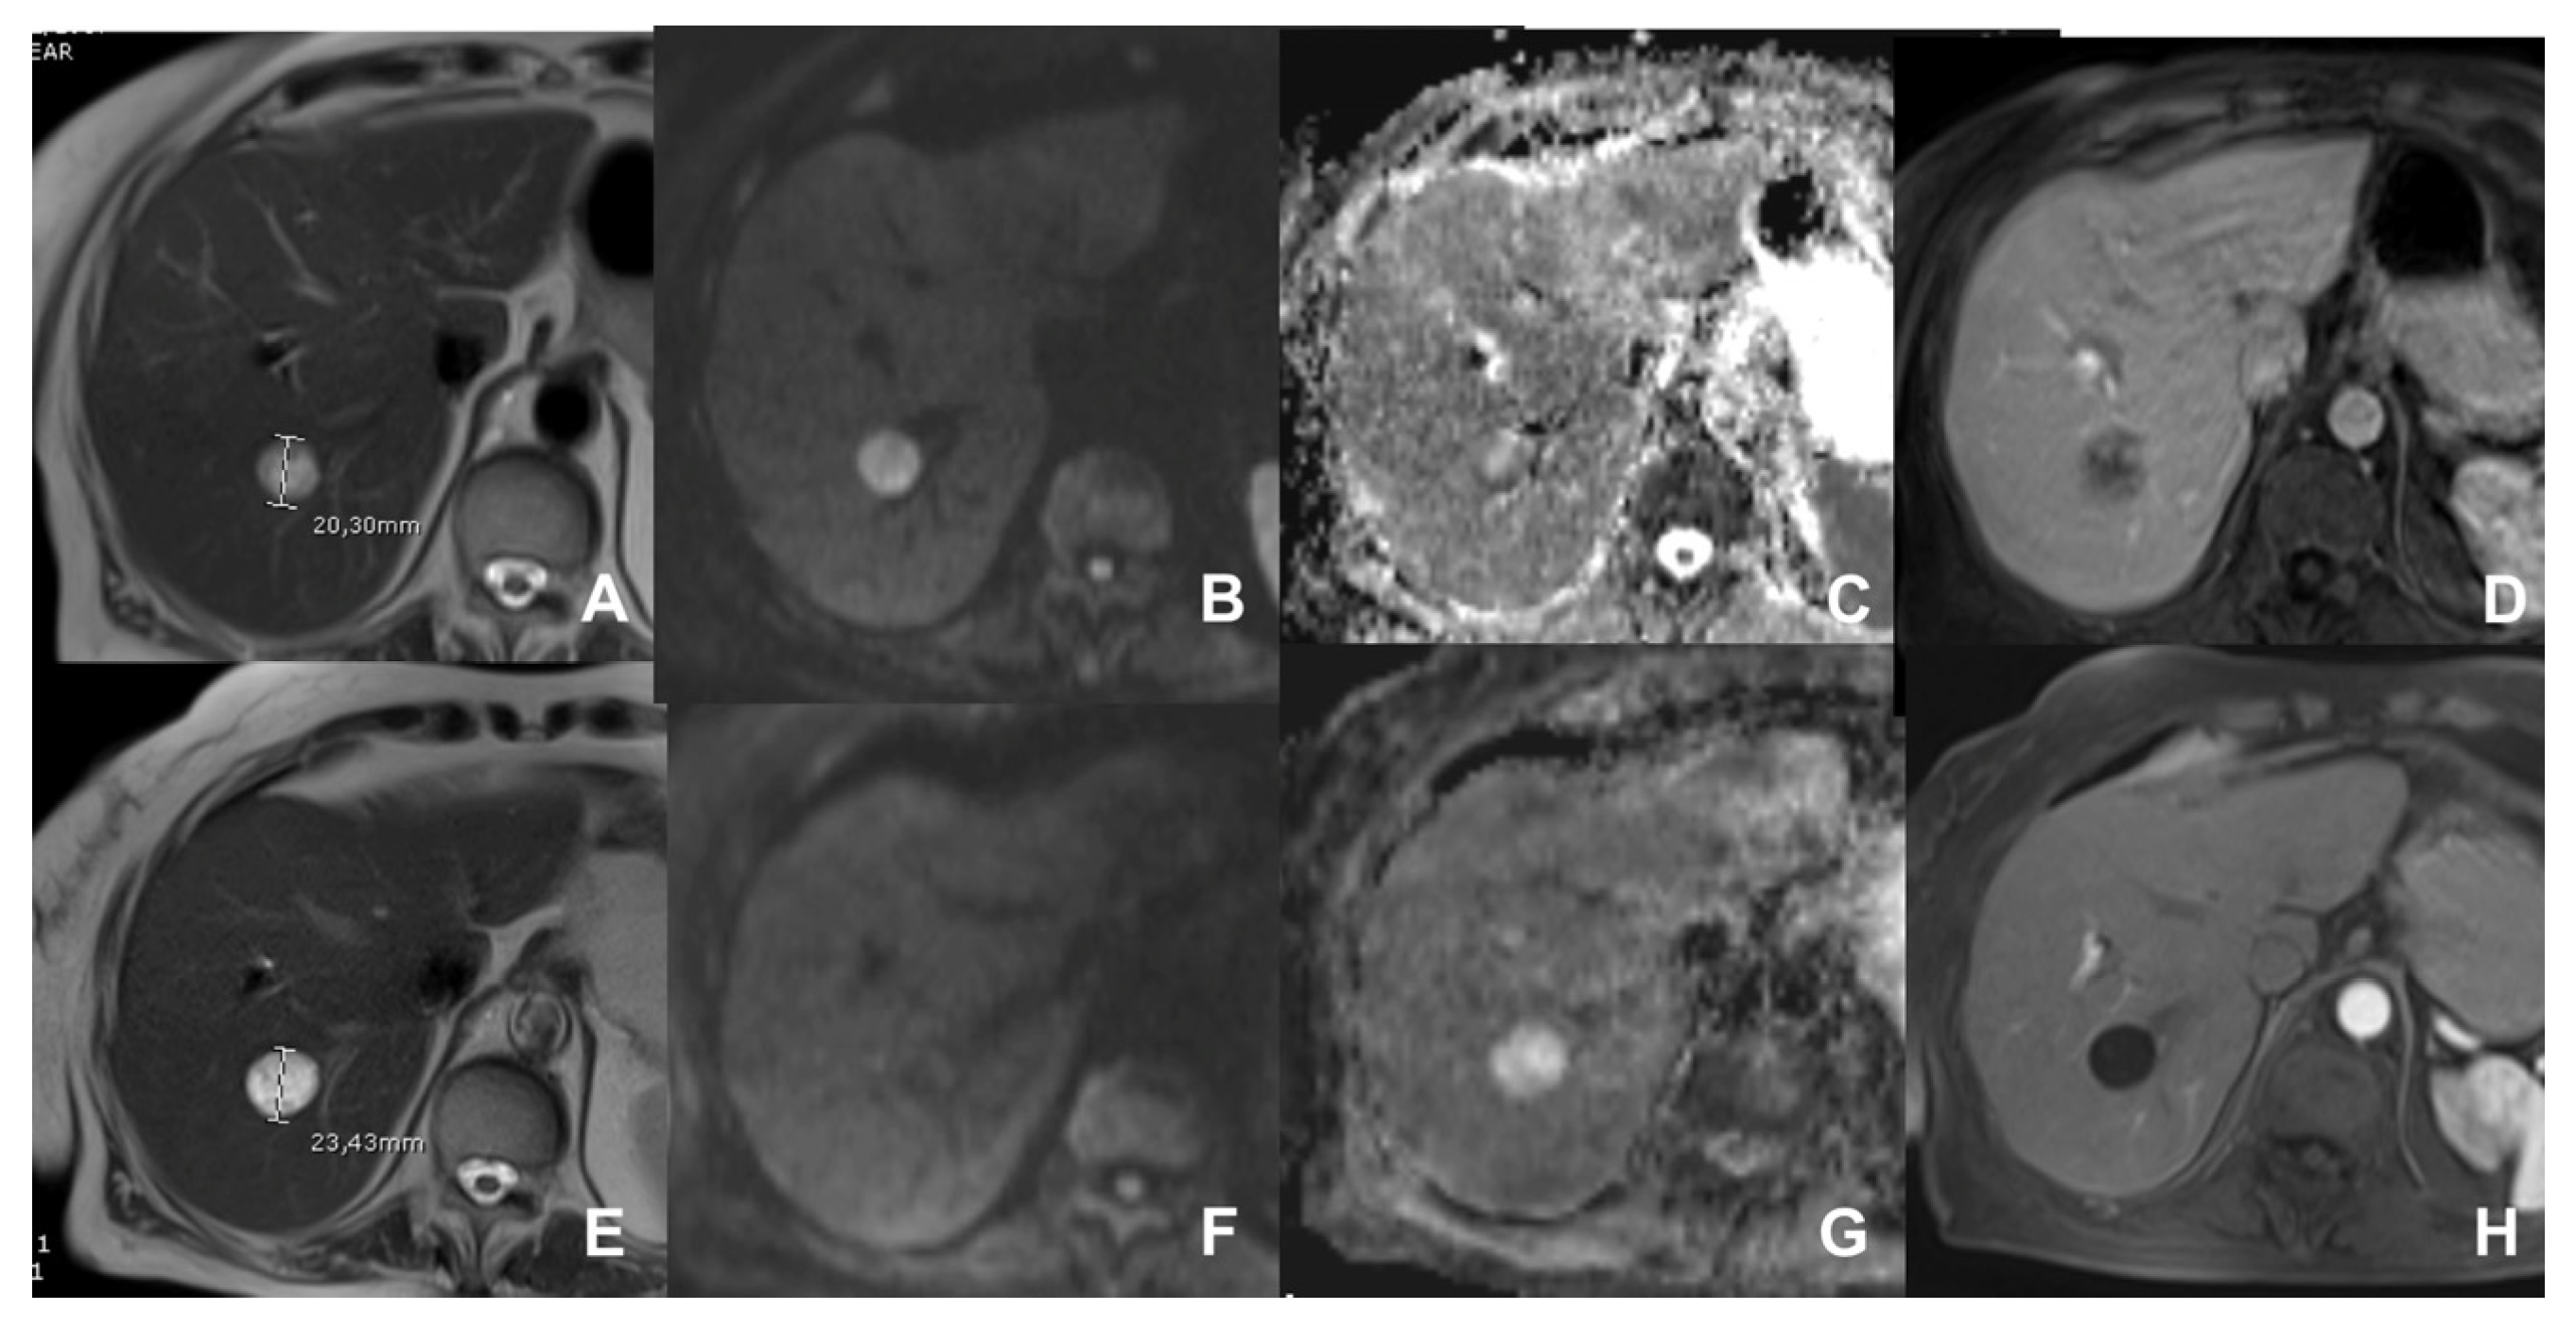

- Shin, S.K.; Kim, Y.S.; Choi, S.J.; Shim, Y.S.; Jung, D.H.; Kwon, O.S.; Choi, D.J.; Kim, J.H. Characterization of small (≤3 cm) hepatic lesions with atypical enhancement feature and hypointensity in hepatobiliary phase of gadoxetic acid-enhanced MRI in cirrhosis: A STARD-compliant article. Medicine 2017, 96, e7278. [Google Scholar] [CrossRef] [PubMed]

- Inchingolo, R.; De Gaetano, A.M.; Curione, D.; Ciresa, M.; Miele, L.; Pompili, M.; Vecchio, F.M.; Giuliante, F.; Bonomo, L. Role of diffusion-weighted imaging, apparent diffusion coefficient and correlation with hepatobiliary phase findings in the differentiation of hepatocellular carcinoma from dysplastic nodules in cirrhotic liver. Eur. Radiol. 2015, 25, 1087–1096. [Google Scholar] [CrossRef]

| GRE T1 3D DYNAMIC | AXIAL | PRE-ART 25″-PORTAL 70″-LATE 180″ | YES (if the lesion is hypervascular) | Benign hypervascular hepatocitic lesions appear hyperintense in HBP | |

| Cirrhotic liver: characterization of FLL/Follow-up after treatment | HASTE T2 | AXIAL | -- | -- | Anatomy and liquids analysis |

| DWI b 0–50–400–800 | AXIAL | -- | -- | High signal in b 800 suspicious for HCC | |

| GRE T1 IN/OUT | AXIAL | -- | -- | Steatosis | |

| GRE T1 3D DYNAMIC | AXIAL | PRE-ART 25″-PORTAL 70″-LATE 180″ | YES (if the lesion shows atypical enhancement) | Hypointensity in HBP suspicious for HCC | |